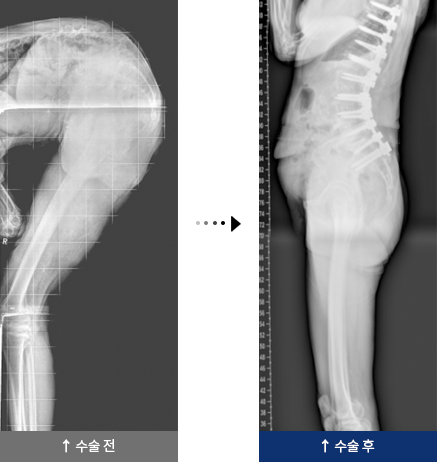

퇴행성 요추 후만증